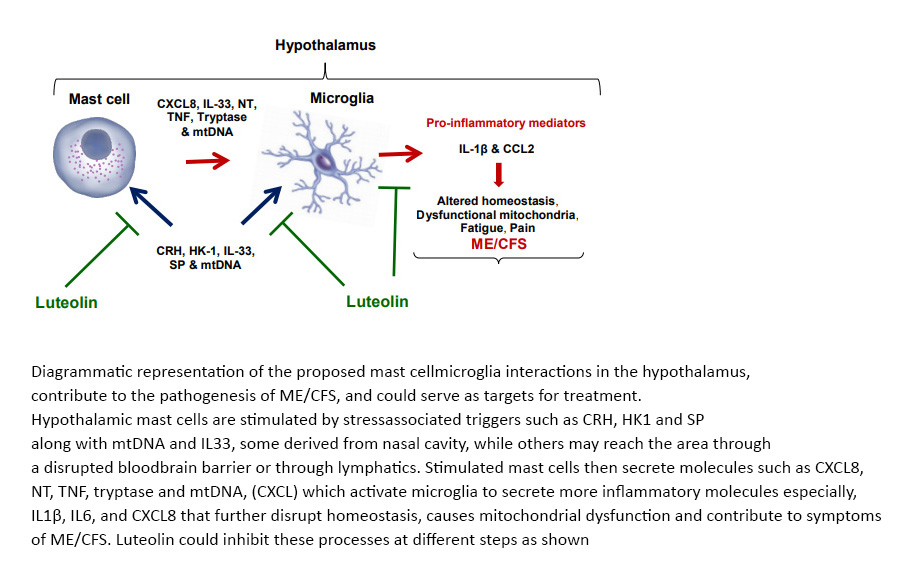

8) Hypothalamus